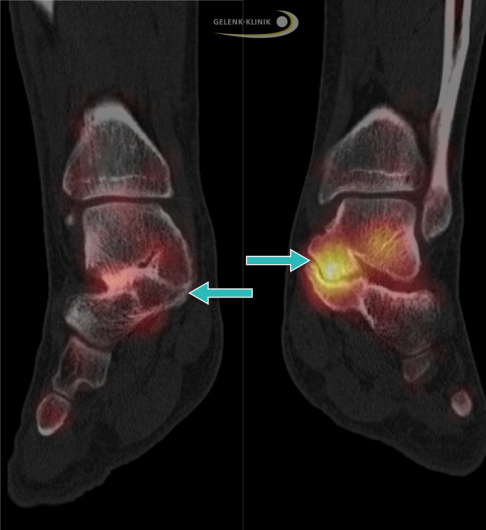

Die Single-Photon-Emissionscomputertomographie (SPECT) ist eine nuklearmedizinische Untersuchung, bei der eine radioaktiv markierte Substanz (Tracer) zur Lokalisation von Regionen mit einem veränderten Knochenstoffwechsel verabreicht wird. Dank dieser Bildgebung lassen sich Koalitionen mit einem aktiven Knochenstoffwechsel genau identifizieren. Die Traceranreicherung im Bereich der Verwachsung steht in einem starken Zusammenhang mit den beschriebenen Schmerzen.

SPECT-Untersuchung, links: reizfreie Koalition ohne Tracer-Anreicherung. Rechts: aktiver Knochenstoffwechsel einer Koalition zwischen Sprungbein und Fersenbein bei einem Erwachsenen mit beginnender Arthrose. Die starke Anreicherung des Tracers steht im Zusammenhang mit den Schmerzen des Patienten. © Gelenk-Klinik